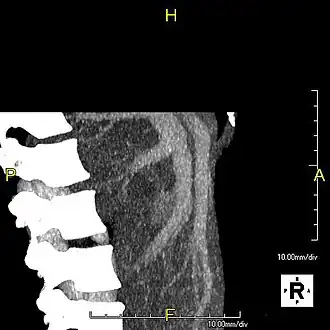

With the recent advances of noninvasive imaging, living liver donors usually have to undergo imaging examinations for liver anatomy to decide if the anatomy is feasible for donation. The evaluation is usually performed by multidetector row computed tomography (MDCT) and magnetic resonance imaging (MRI). MDCT is good in vascular anatomy and volumetry. MRI is used for biliary tree anatomy. Donors with very unusual vascular anatomy, which makes them unsuitable for donation, could be screened out to avoid unnecessary operations.

Phase contrast CT image. Contrast is perfusing the right liver but not the left due to a left portal vein thrombus.